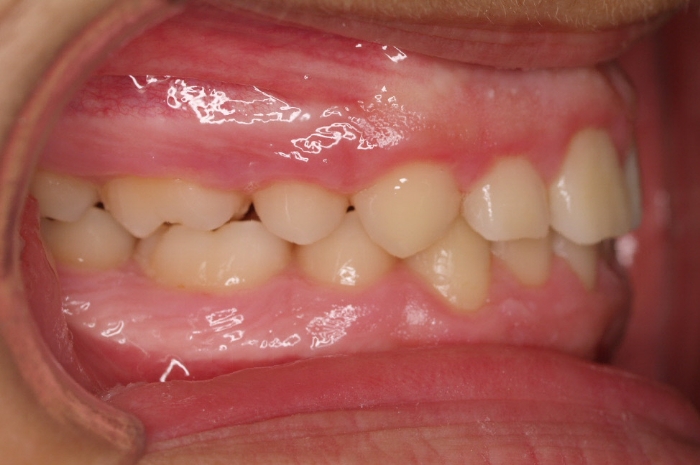

El paciente M.C. acude a nuestra consulta por:

– Apiñamiento importante

– Perfil convexo

– Forma arcada estrecha

-sobremordida

Fotos antes tratamiento: